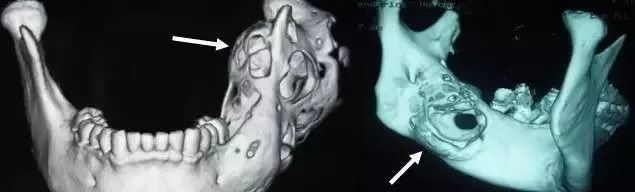

怎么治疗是难点。很显然,病变的下颌骨要切除掉。然而切除简单,修复难。下颌骨的修复是口腔颌面部最为棘手的手术之一,之所以棘手,其难点在于:颌骨的修复重建对咬合功能恢复要求较高,手术中对位稍有偏差即可出现咬合问题,导致患者术后无法正常吃饭生活。

杭州市第一人民医院的口腔颌面外科团队应用基于CAD/CAM技术和快速原型技术设计的血管化腓骨瓣,完美地重建了小莫半侧下颌骨缺损。

术中,应用塑形导板将依计算机设计切取的腓骨塑形后转到下颌骨缺损区。整台手术非常成功,接下来,小莫可以通过种植牙治疗完成正常食物咀嚼了。